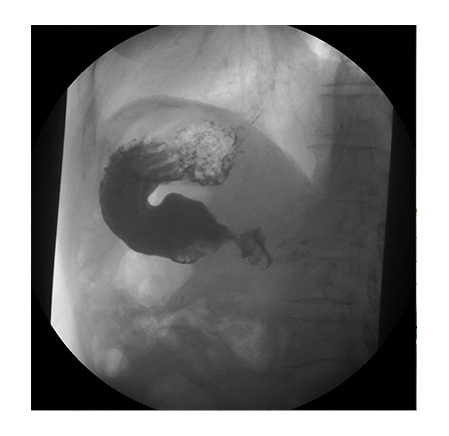

A modern digital imaging system provides for high image quality. A table for images and a vertical stand are fitted out with large format detectors. It provides for the comfortable performance of any examinations including that of large anatomical regions. Besides, the image has high spatial resolution with the minimum exposure dose for the patient. The high resolution ensures imaging of even minor details in the image, which is a quality guarantee of diagnostics performed.

High diagnostic image quality

- High spatial resolution

- State-of-the-art analysis of examination findings